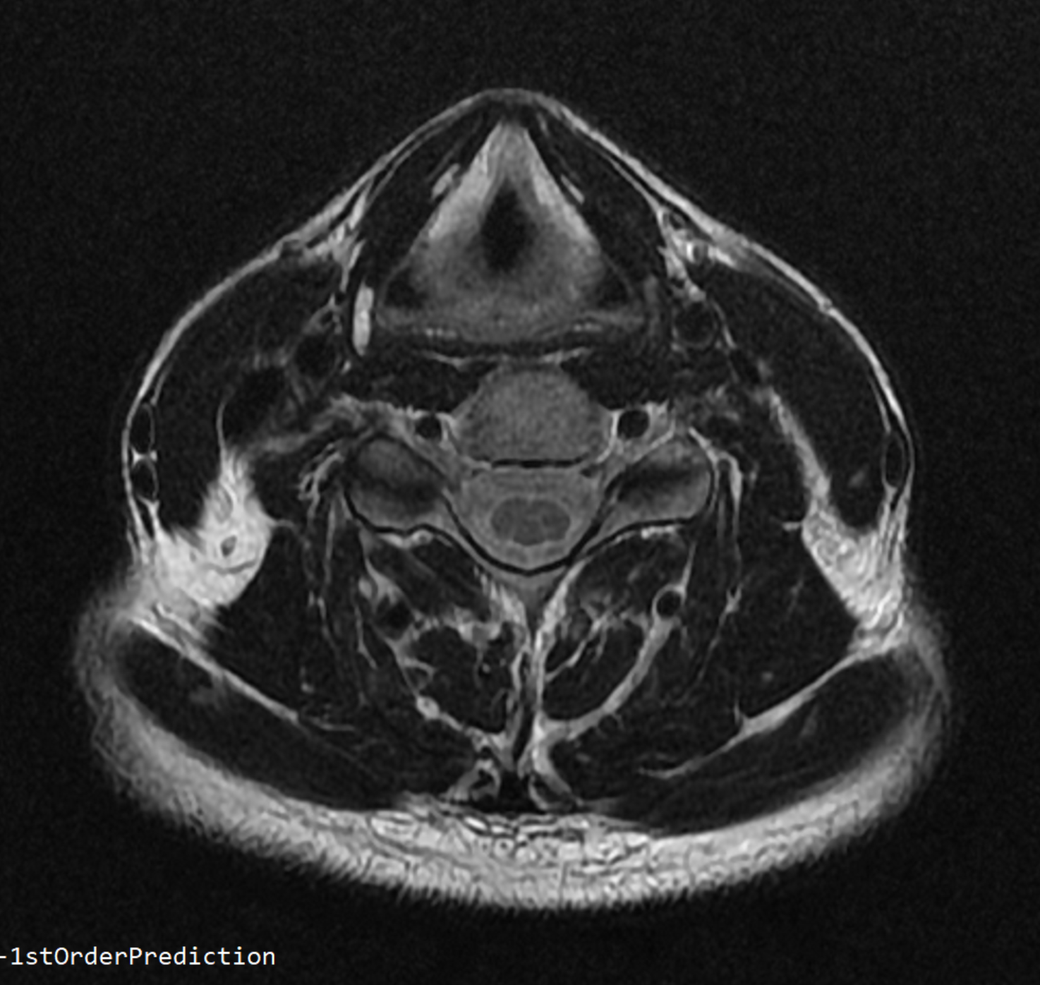

안녕하세요 목 경추 상단부터 순서대로 mri 촬영인데요

전체적으로 봐주시면 감사하겠습니다

• 3번 째 사진